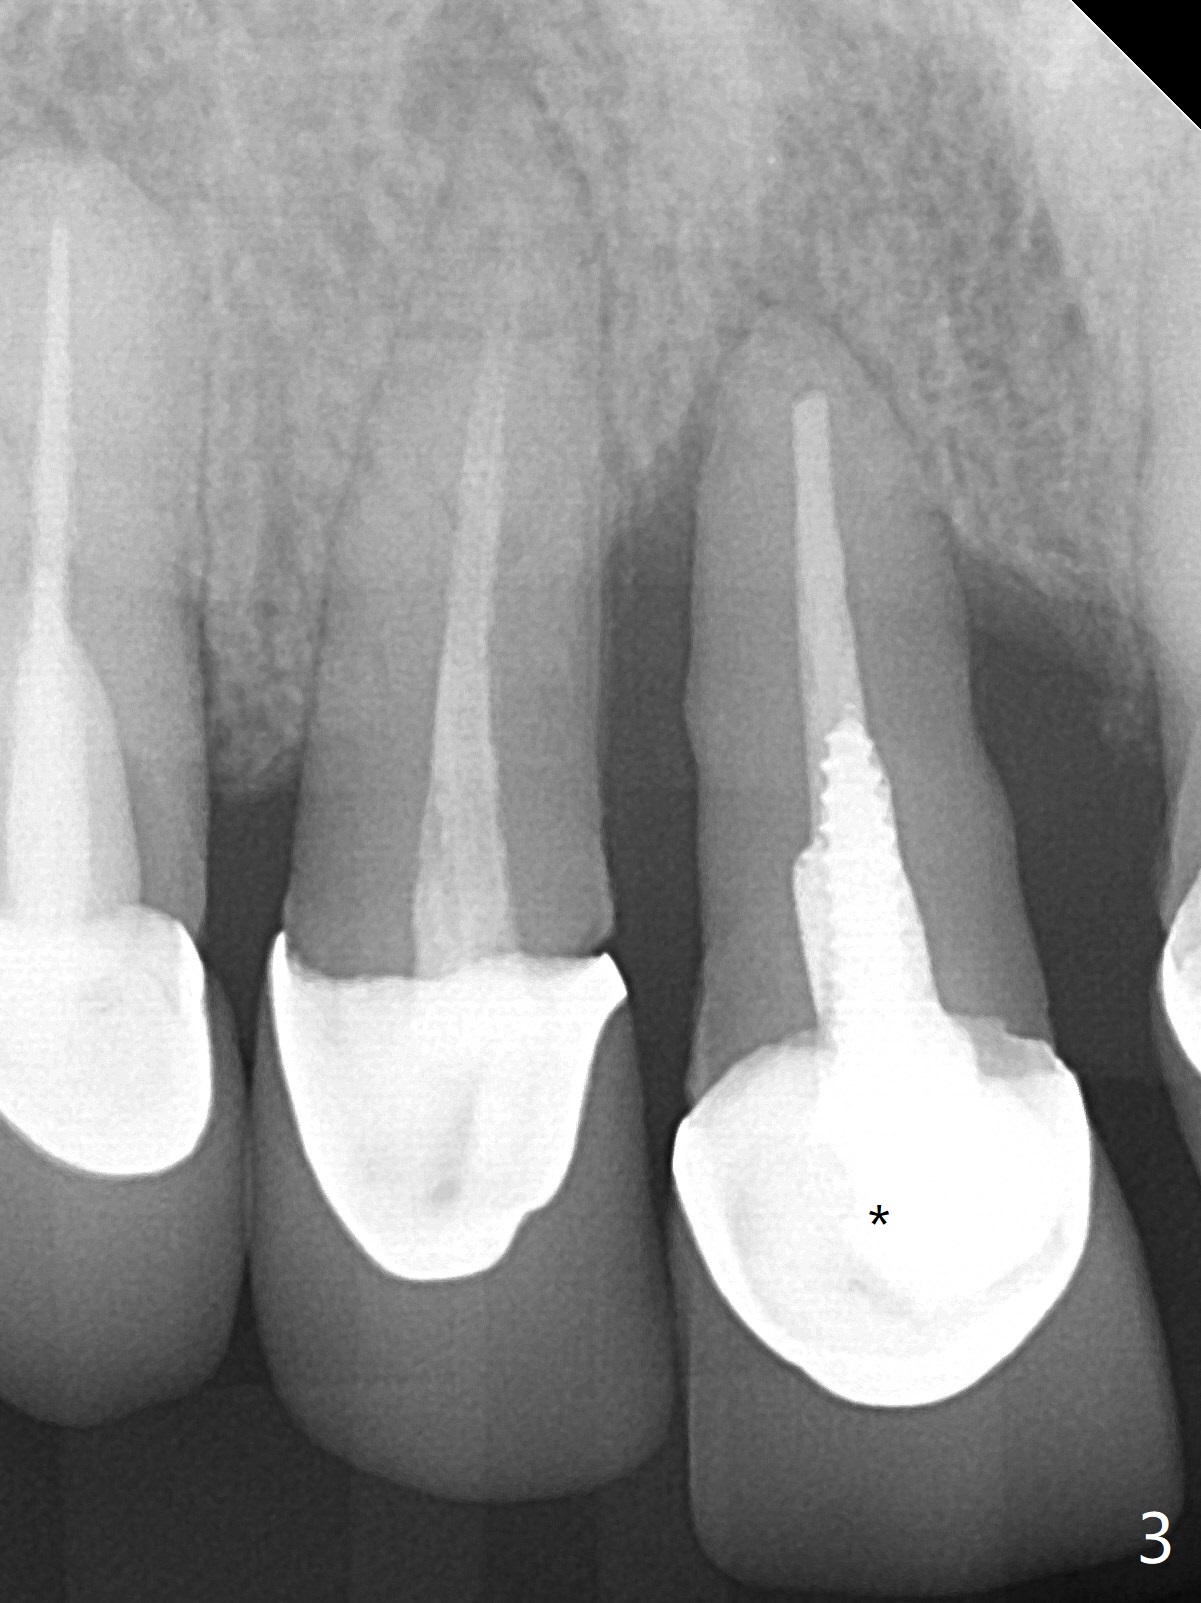

45岁女,害怕治疗,5年多没就医,右上1移位(图一(*),二),严重骨吸收(图三)。深洗后,即刻种植,由于牙龈7毫米长(图四,五)和使用粘性骨粉(骨壁再生),植体可以植浅些(图四:箭头)。上颌深洗一周后,除了患牙,牙龈红肿消除很多(图六,七)。